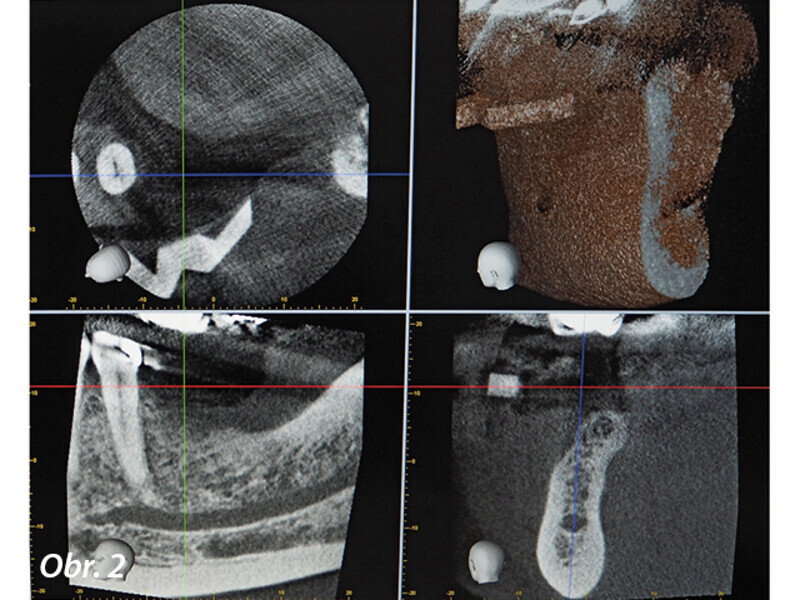

Dynamická navigace pro přesnou implantaci v případech kritické anatomie